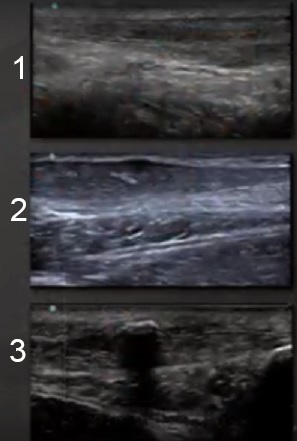

Foot & Ankle Tendon Tears Image